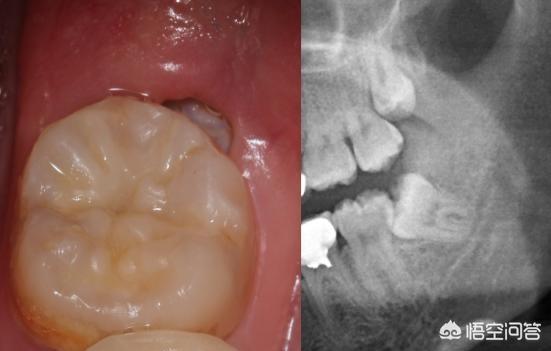

阻生智齿龈瓣覆盖,影响咀嚼,水激光切除,术后立即止血.

智齿

齿冠周炎是口腔内部智齿周围没有完全萌出,牙龈内部肌体抵抗力降低